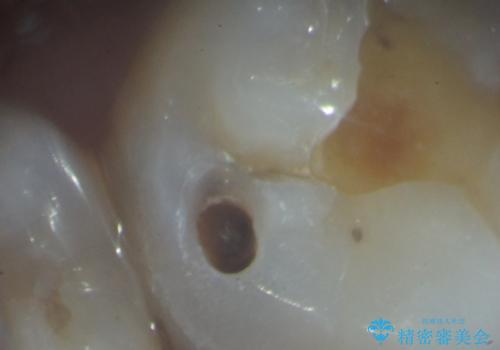

X線検査により外から見てもわからない虫歯が認められたので、マイクロスコープ下で丁寧かつ徹底的に虫歯を除去しセラミックインレーによる修復を計画します。

マイクロスコープを用いることで歯の微細な硬さや虫歯の広がりをすみずみまで精査することができます。